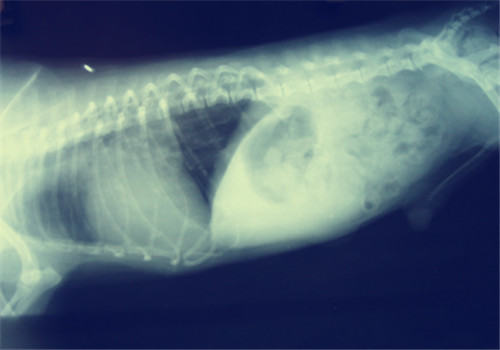

肥胖对照图

运动不耐受与心肺疾病史肥胖的主要并发症之一,随着犬的体重增加,其心率,心室容量、血压及血容量也会随之而升高。因此对于心脏的负荷也随之增加,长时间的超负荷很容导致心脏疾病的发生。同时由于脂肪太多,大量的堆积在胸壁和腹壁,胸腔和腹腔的运动性变差,呼吸收到一定的压迫。由于心肺功能的不全,加上运动时需要克服重力的作用也增大,从而导致动物运动的不耐受。

肺脏疾病